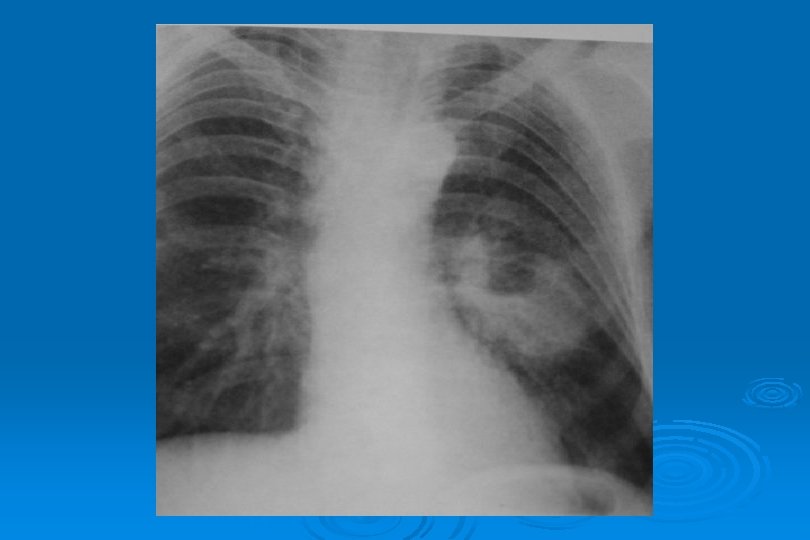

LEGIONELLA PNEUMONIA Chest radiograph All patients with Legionnaires' disease have radiographic abnormalities by day three The most common pattern is a patchy unilobar infiltrate which progresses to consolidation Diffuse, interstitial infiltrates, pleural effusions also are commonplace Immunosuppressed patient may have rounded pleural based opacities Cavitation is commonly seen in the immunosuppressed patient receiving corticosteroids Radiographic improvement lags behind clinical response by several days Complete resolution of infiltrates on chest radiograph occurs over one to many months